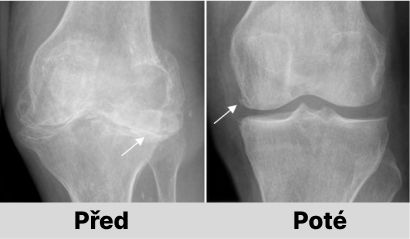

Jaroslava Melicharová: Určitě to možné je. Pokud nedošlo k nevratným patologickým změnám v kostech, lze vše napravit odstraněním příčiny pomocí ArtiZynt. Náš výzkum dokazuje, že již za 1-1,5 měsíce nepřetržitého užívání ArtiZynt je možné obnovit klouby i u těžkých forem osteoartrózy a artrózy.

U 99,2 % osob trpících různými revmatickými onemocněními (osteochondróza, artróza, artritida, osteoporóza, dna, dysplazie kloubů, sklerodermie atd.) došlo během 2 měsíců po užívání ArtiZynt k úplnému uzdravení kloubů. Osoby se zbavily bolesti a dalších příznaků a také pohyblivost kloubů se vrátila do normálu.